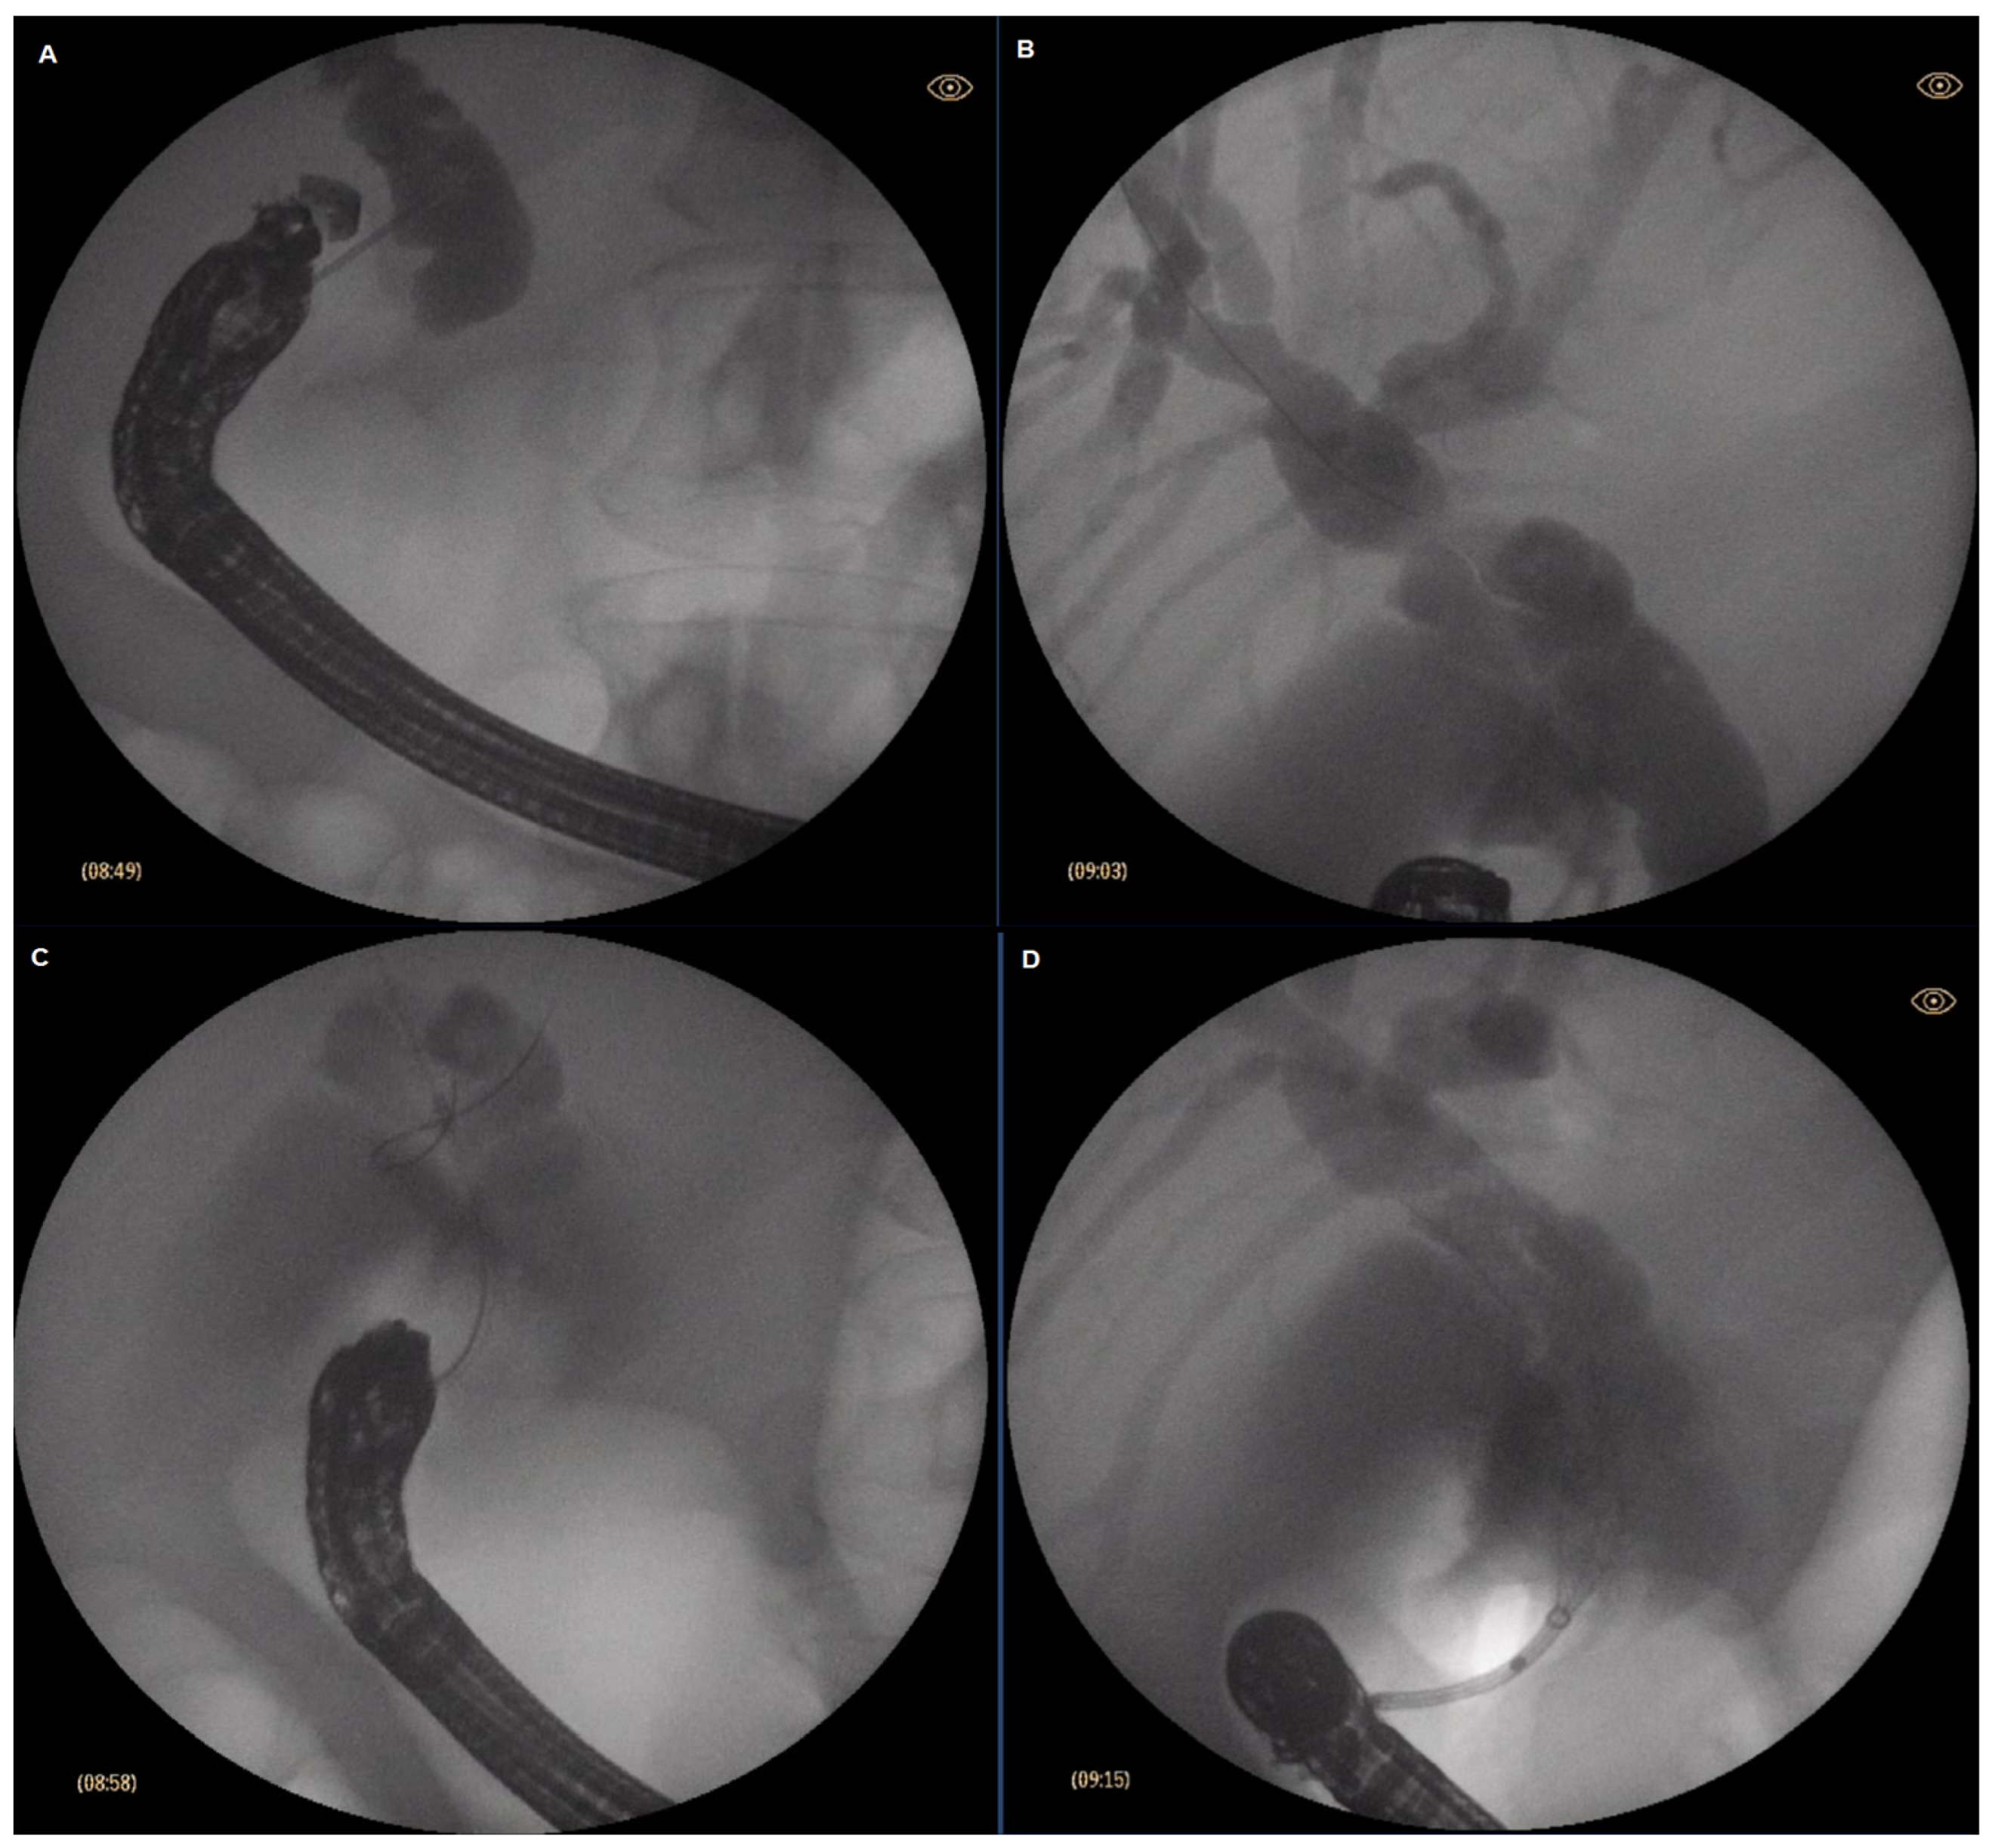

4. Technique Description